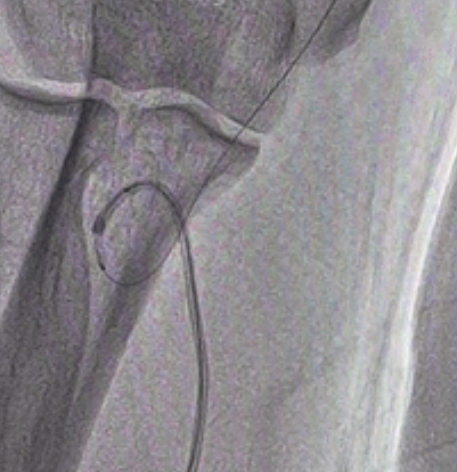

图5 回拉导管将弯曲血管拉直

“α”型迂曲或“Ώ”型迂曲的血管在PTCA导丝通过后有时5F导管都无法跟进时可以尝试“BAT”技术(balloon at tip),根据血管直径选择球囊直径,一般为2.0X20mm普通球囊,沿导丝送球囊在导管头端,一半在导管头外,一半在导管内,轻轻打起球囊(4-6ATM),使扩张的球囊和导管融为一体,再推送导管和球囊前行,由于稍微扩张的球囊更为柔顺,不会划破血管,可以弯曲,通过性更好,可能带着导管通过严重迂曲处,当导管到达肱动脉处时回拉导管,有可能将成环状的迂曲拉直从而完成手术(见图示1-5)。